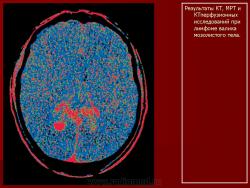

Лимфомы головного мозга.

1.Uv_.Slayd48.JPG2.Uv_.Slayd49.JPG3.Uv_.Slayd50.JPG4.Uv_.Slayd51.JPG5.Uv_.Slayd52.JPG6.Uv_.Slayd53.JPG7.Uv_.Slayd54.JPG8.Uv_.Slayd55.JPG9.Uv_.Slayd56.JPG10._Uv.Slayd57.JPG11.Uv_.Slayd58.JPG